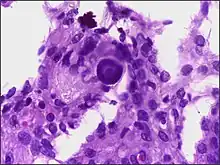

Histologically, meningioma cells are relatively uniform, with a tendency to encircle one another, forming whorls and psammoma bodies (laminated calcific concretions).[16] As such, they also have a tendency to calcify and are highly vascularized.